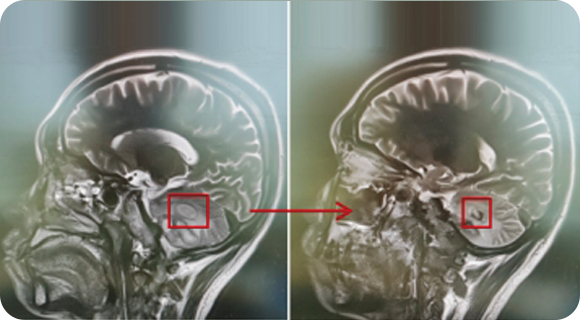

精通顱內(nèi)動脈瘤介入栓塞和手術(shù)夾閉雙技術(shù),系統(tǒng)掌握腦動靜脈畸形、頸內(nèi)動脈海綿竇漏、硬腦膜動靜脈漏等顱內(nèi)血管疾病的診療和手術(shù),精通頸動脈、椎動脈狹窄的血管內(nèi)重建技術(shù),以及頸動脈狹窄的內(nèi)膜剝脫手術(shù)技術(shù)。在顱內(nèi)腫瘤、椎管內(nèi)腫瘤、顱腦損傷、高血壓腦出血等疾病的診治和手術(shù),腦功能性疾病立體定向手術(shù)治療等方面也積累了豐富的經(jīng)驗。